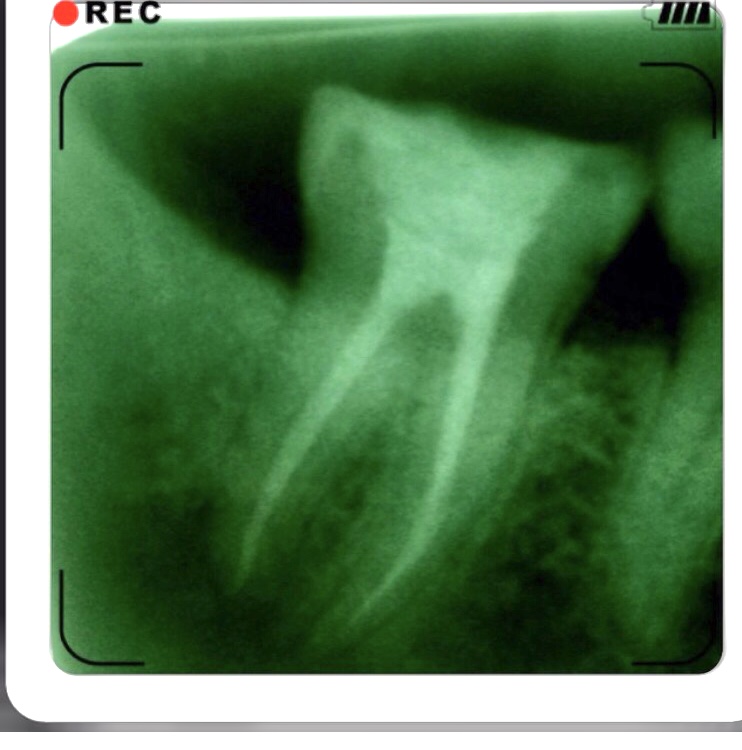

RCT #31

RCT #18